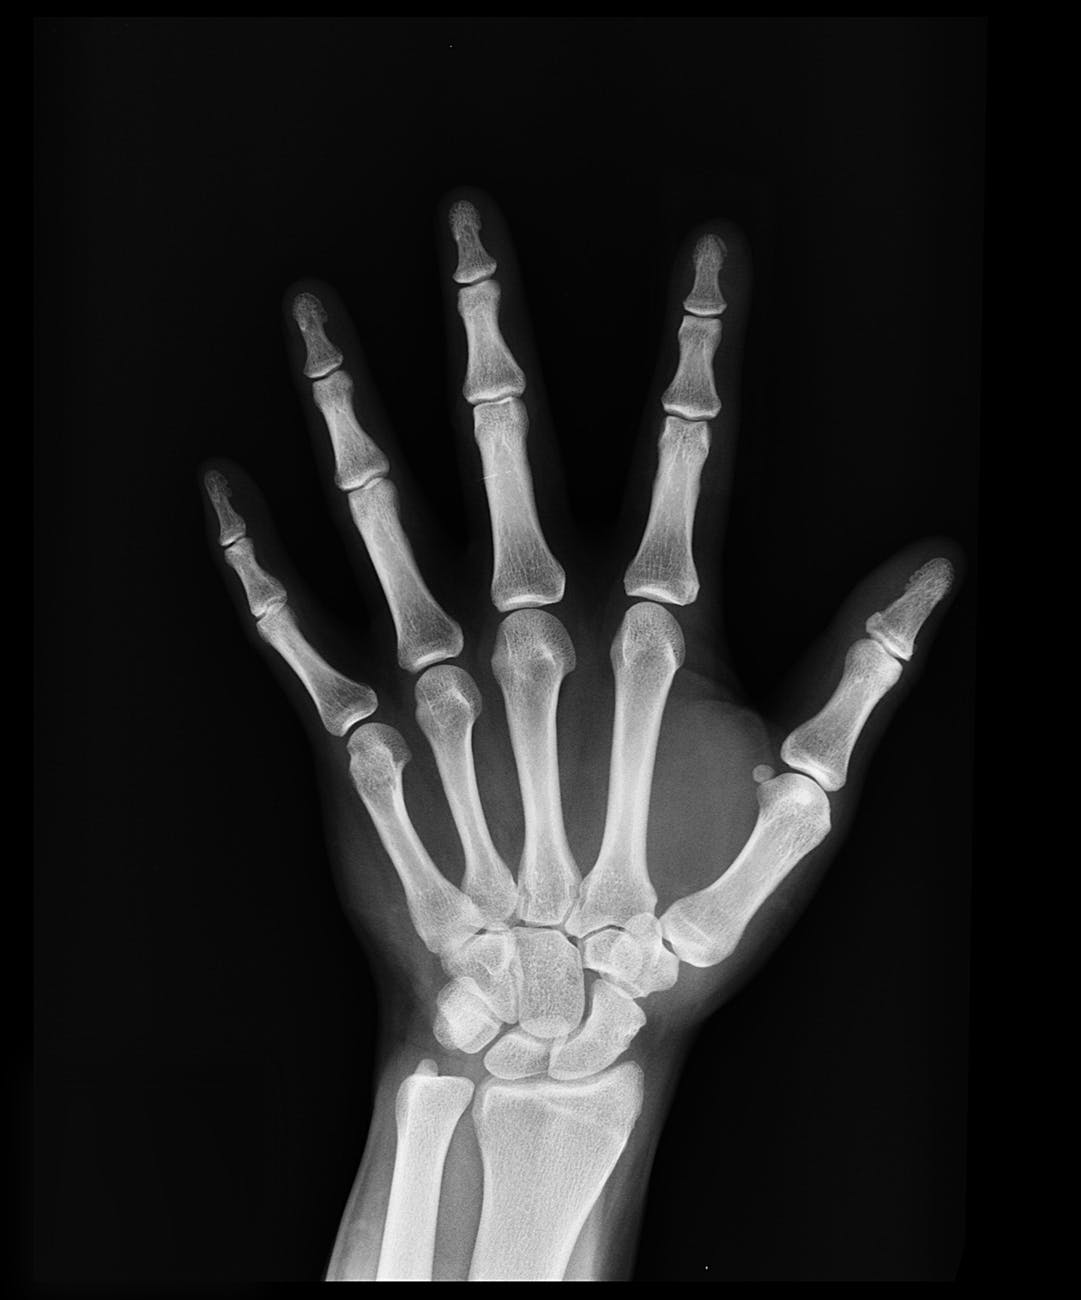

hygiene is the possibility of carpal tunnel syndrome. Carpal tunnel syndrome (CTS) causes inflammation (and fluids) of

the wrist and surrounding tissues. Dental professionals especially are at risk

because of the repetitious motions in the hand and wrist. This is also is

defined as repetitive motion disorders

(RMDs). I never knew there was a

name for my repetitious motions. It makes a lot of sense. Bad habits in

instrumentation directly correlate with injuries. Some common symptoms are

numbness, tingling, and pain in the wrist/hand areas (Donatella, 2019). This is

part of the reason I am getting my bachelors. It is a back up and safety net

just in case in the future I experience CTS.